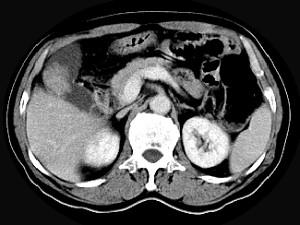

问题 男,45岁,右季肋区疼痛,Murphy征阳性,B超提示胆囊息肉,CT所见如图,最可能的诊断是 ( )

选项 A、胆囊转移癌 B、胆囊腺肌增生症 C、胆囊癌 D、慢性胆囊炎 E、胆囊息肉

答案 C